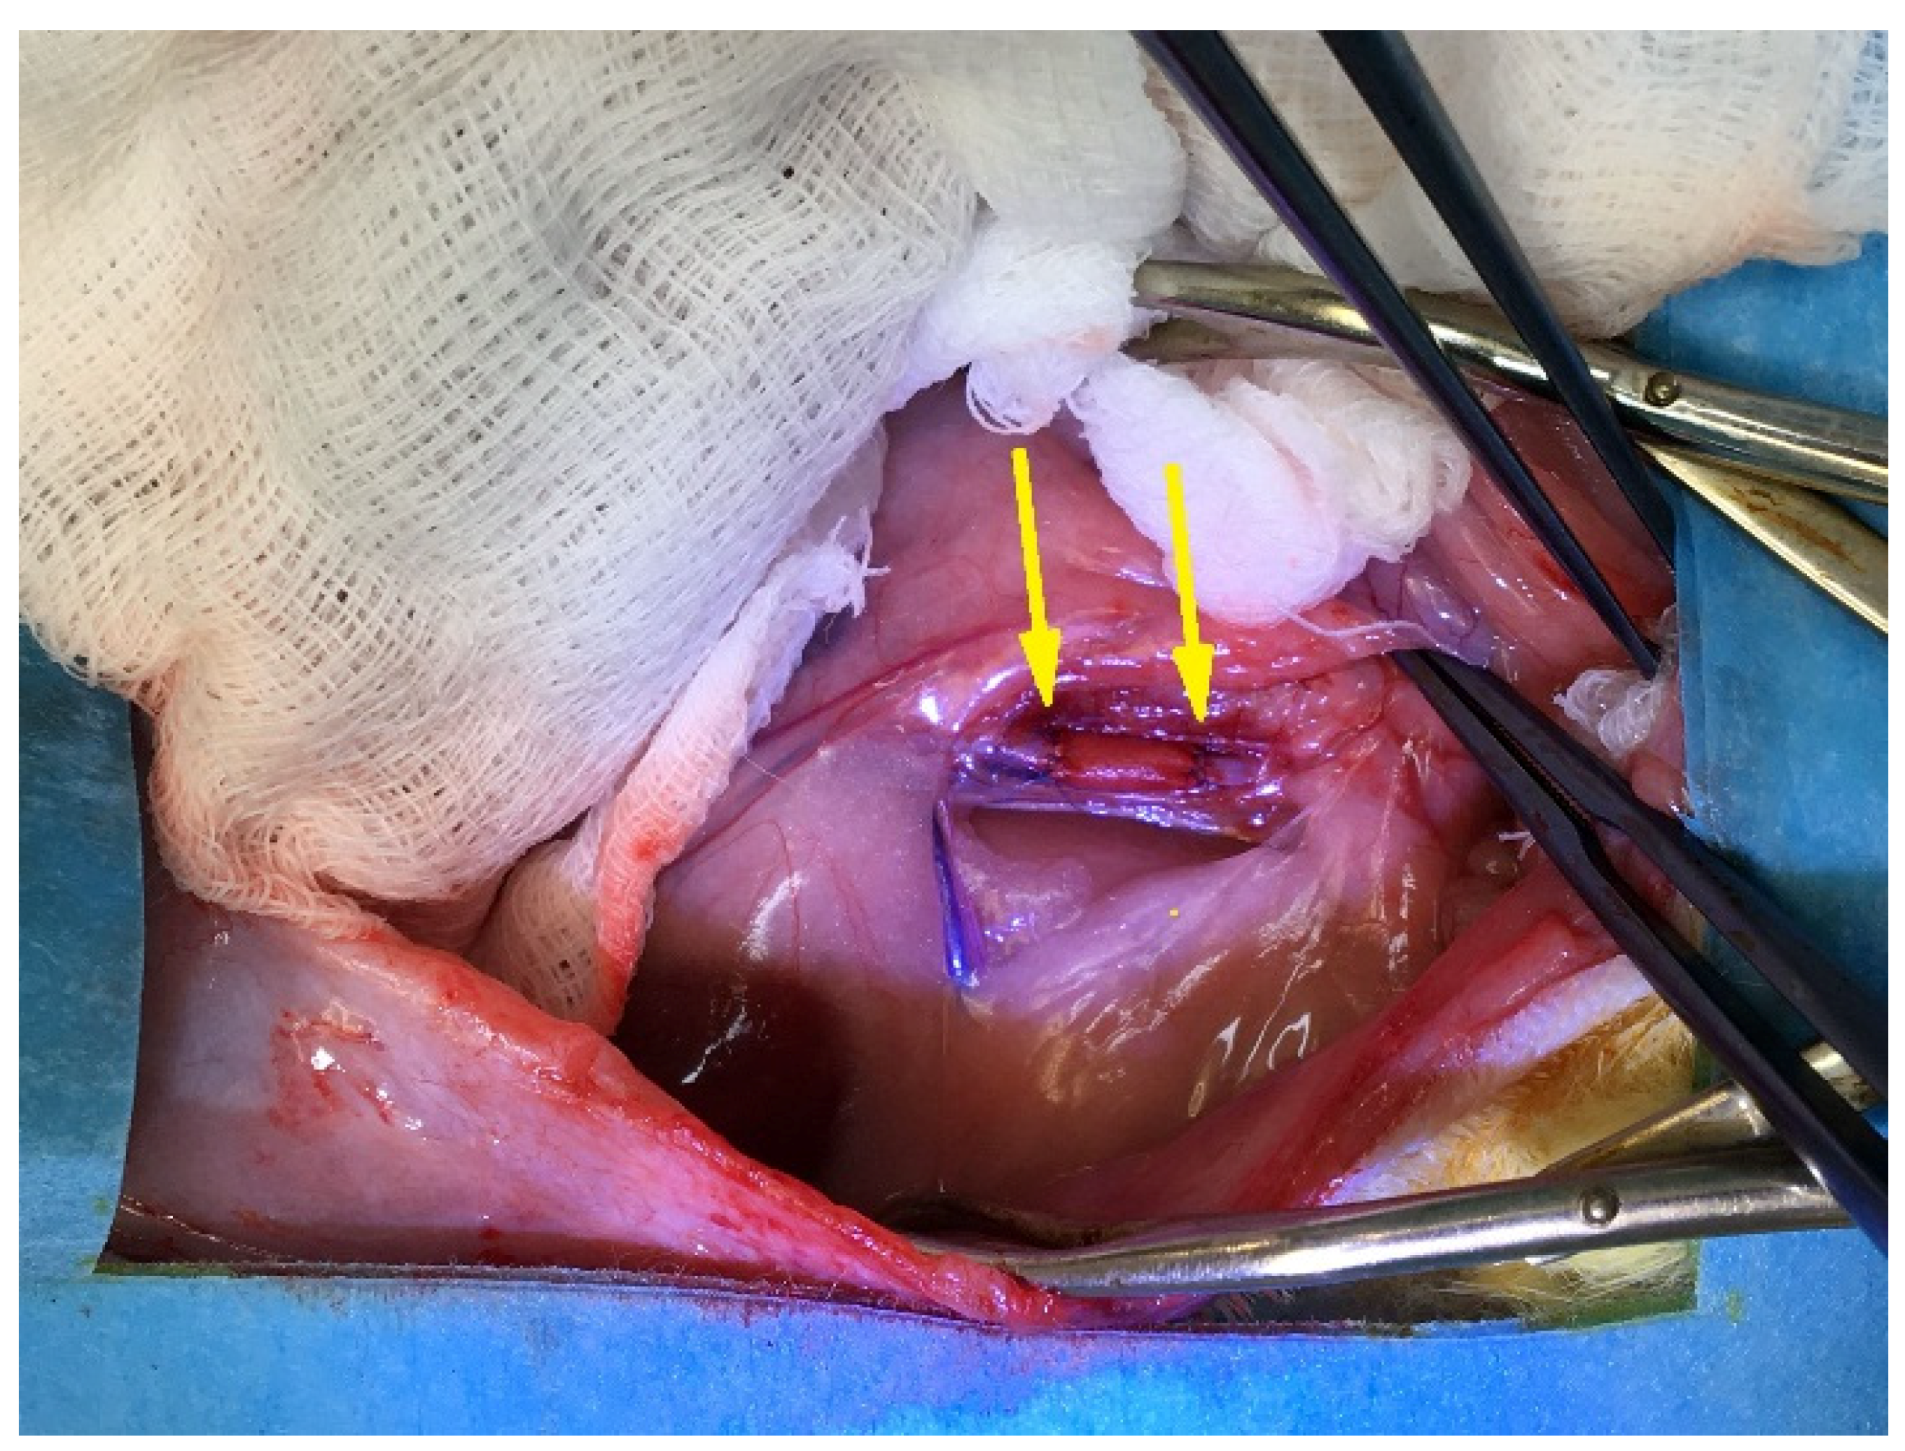

2.5.3. Surgery

3.2. PCL Graft Observation in Dynamics